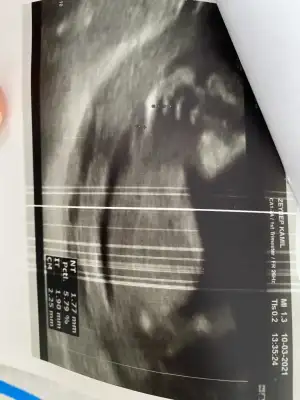

12+6. Tahmin eder misiniz lütfen 🌸

Eklentiler

• D71C8A73-5EF5-412B-9994-87F425645397.webp

D71C8A73-5EF5-412B-9994-87F425645397.webp

27,2 KB · Görüntüleme: 61

• F9AA6519-BCB9-4C2C-9D1F-89A43E806AEE.webp

F9AA6519-BCB9-4C2C-9D1F-89A43E806AEE.webp

23,3 KB · Görüntüleme: 49

• D2AD2A0E-2ADB-4078-AFA5-98CE87F7AA6E.webp

D2AD2A0E-2ADB-4078-AFA5-98CE87F7AA6E.webp

32,6 KB · Görüntüleme: 56